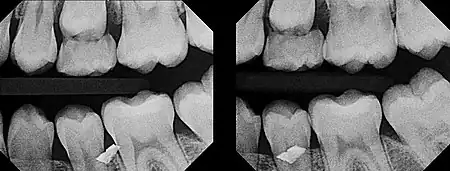

In 1909, Charles A. Clark described a radiographic procedure for localizing impacted teeth to determining their relative antero-posterior position.[1] If the two teeth (or, by extension, any two objects, such as a tooth and a foreign object) are located in front of one another relative to the x-ray beam, they will appear superimposed on one another on a dental radiograph, but it will be impossible to know which one is in front of the other. To determine which is in front and which is behind, Clark proposed his SLOB rule, as a complicated set of three radiographs, but which can be simplified as follows using just two:

- Expose another film while angle of the x-ray beam has been changed. If an object moves in the same direction as the source of the x-ray beam, it is lingual to the other object. If the object moves in the opposite direction of the source, it is buccal to the other object.

- Same Lingual; Opposite Buccal

In 1952, Richards amended this rule using only 2 radiographs,[2][3] asserting that the object positioned more buccally will move more relative to the object positioned more palatally or lingually.